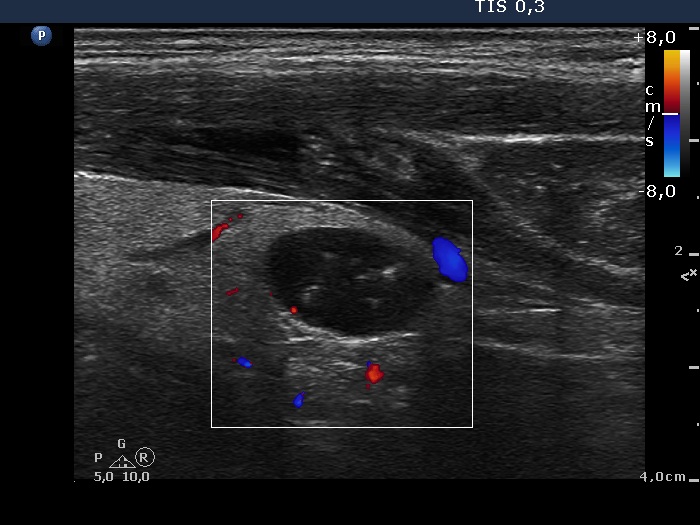

Intranodular hyperechogenic figures - case 284 (ultrasonographic picture 5)

Right lobe, longitudinal view, color Doppler mode. The nodule shows no vascularization.